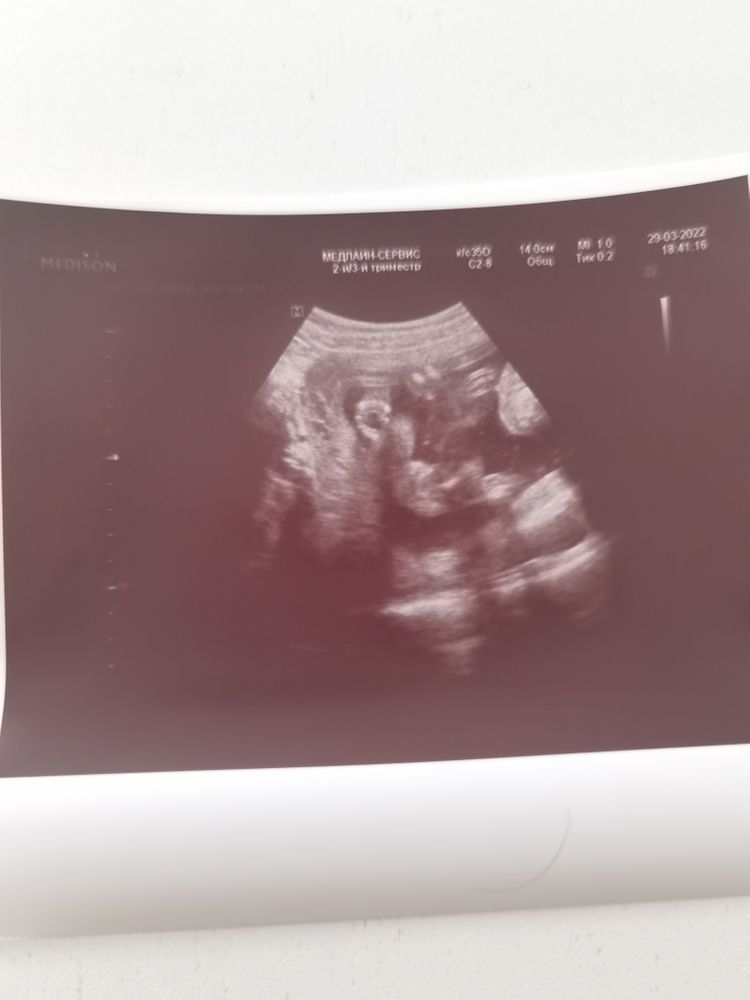

Пол малышаЯ не удержалась и сходила ещё раз на узи, только пол посмотреть. Аппарат, конечно, намного хуже чем в жк оказался. И сначала снова увидили что-то мальчишечье между, но потом оказалось, что это пуповина, даже допплер включили проверить.

В итоге пол на фото, это же точно пирожок? 🥰☺️

Да, это девчушка😻у нас тоже такой пирожочек был на экране💝

Мне кажется, что пирожок. У нас с такого же ракурса пистолет отчётливо виден был))